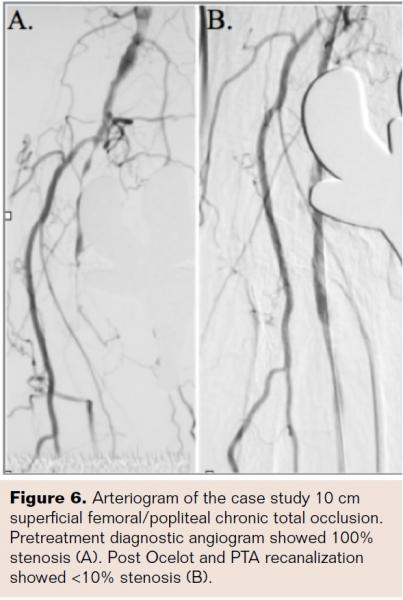

Case Example: Low-Fluoroscopy CTO Crossing Using the Ocelot Catheter

A representative low-fluoroscopy CTO case is shown in Figure 6. A 68-year-old female presented with multiple risk factors for cardiovascular disease and PVD, including history of smoking, hypertension, hyperlipidemia, diabetes mellitus, history of myocardial infarction, and ischemic cardiomyopathy (ejection fraction 35%). The patient presented with intermittent claudication for several years and rest pain over the last 6 months, Rutherford Class IV, with no critical limb ischemia and with ankle brachial index of 0.5 on the right leg. Angiogram of the right lower extremity showed complete occlusion of the left distal SFA to P3 popliteal segment (Figure 6). Further complicating the matter, the patient had a prosthetic knee replacement, which blinded A/P x-ray viewing of the occluded segment. The 10 cm 100% CTO lesion was crossed stand-alone using the OCT guided Ocelot catheter. The total crossing time was 2 minutes and 17 seconds. CTO crossing fluoroscopy was measured at 12 seconds (0.2 mins) and included angiographic confirmation of distal wire advancement following distal cap crossing (Figure 7). The OCT imagery during the crossing highlighted a true lumen recanalization with eccentric disease burden composed of mostly fibrin rich de novo plaque and a moderate calcium nodule (Figure 8). The lesion was then treated with angioplasty (Chocolate balloon; Cordis Corporation). Residual, stand-alone post-therapy stenosis was measured at <10%. Importantly, OCT was able to reliably guide a true lumen crossing in the no-stent popliteal zone even with prosthetic hardware blocking angiographic visualization of the artery.